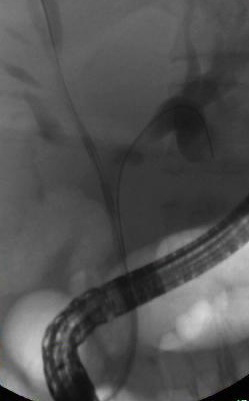

Endoscopic retrograde cholangiopancreatography (ERCP): A procedure which combines x-rays and the use of an endoscope and may be used to obtain a tissue sample.

ERCP allows the physician not only to diagnose, but also to treat abnormalities in the bile ducts and pancreas. Using ERCP, the doctor can open up blocked ducts, perform complex biliary drainage, and remove tissue to be biopsied. ERCP can be used to treat pancreatic cancer by combining it with:

• Insertion of a stent to open a narrowed bile duct and improve quality of life in patients with advanced disease. This procedure must be performed by an advanced interventional endoscopist proficient in using this approach.